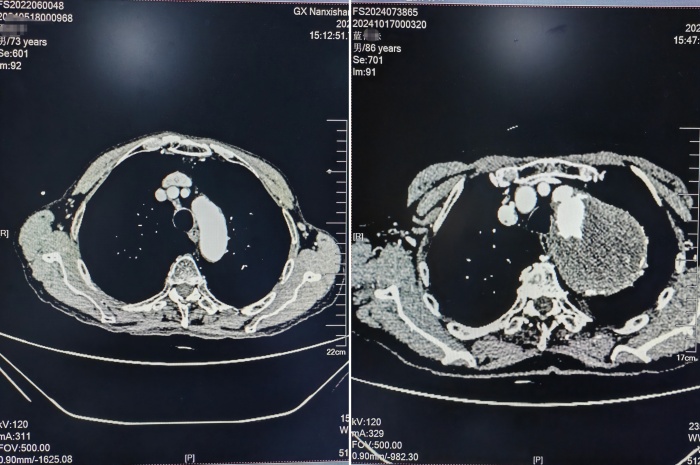

抵达南溪山医院时,蓝大爷的胸背部疼痛仍在持续发作。心脏大血管外科的值班医生迅速给予稳定血压、心率、止痛等对症治疗,待老人生命体征平稳后,进一步护送他进行主动脉夹层CTA检查。检查结果令人震惊:巨大胸主动脉瘤合并附壁血栓形成,动脉瘤直径竟达到82mm,远超正常范围。

正常主动脉与患者主动脉CTA

结合CTA设计的手术方案